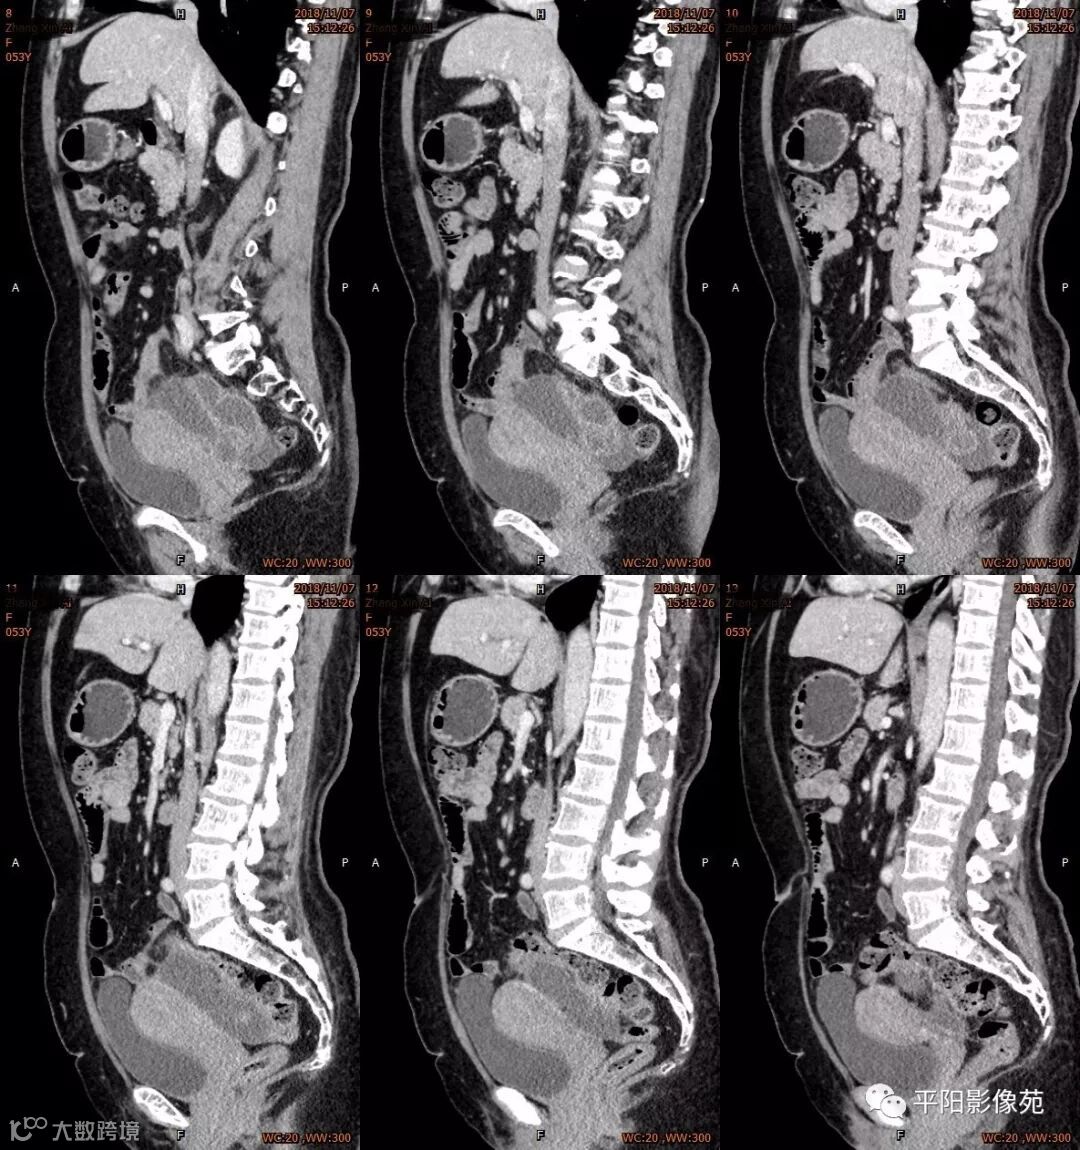

影像特点

右附件区薄壁囊性病变,壁明显强化,边界不清,供血动脉源自子宫动脉,且局部动脉血管增多;其内侧可见卵圆形无强化囊性病灶。

附件区病变多见于卵巢,以囊性为主的病灶多为卵巢囊肿、粘液/浆液性囊腺瘤、皮样囊肿等,这些病灶都具有鲜明瘤体结构,且壁强化多为轻-中度,供血动脉多源自卵巢动脉;而本例患者右附件区薄壁囊性病灶,多位置观察形态为迂曲管状,且壁有明显延迟强化,供血动脉源自子宫动脉,较对侧血管丰富,故而考虑源自输卵管或子宫病变,但子宫发生的薄壁囊性病变较少,多见于子宫肌瘤囊变,完全囊变者少见,且形态轮廓与肌瘤相同为球形故而排除,结合患者腹痛前有感冒病史,且有压痛,因此考虑输卵管积脓可能。其内侧无强化囊性肿块,考虑卵巢囊肿可能。